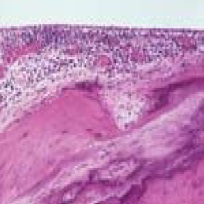

There is hyalinisation of the subepithelial connective tissue of the tympanic membrane and middle ear cavity. Calcifiation is commonly present in these lesions. Osteoneogenesis can also occur within these lesions.

Figure showing histology of tympanosclerosis

Plaques occurring in the tympanic membrane is limited to lamina propria. Deposition of bone due to osteoneogenesis in the attic region may cause fixation of malleus and incus leading on to conductive deafness.